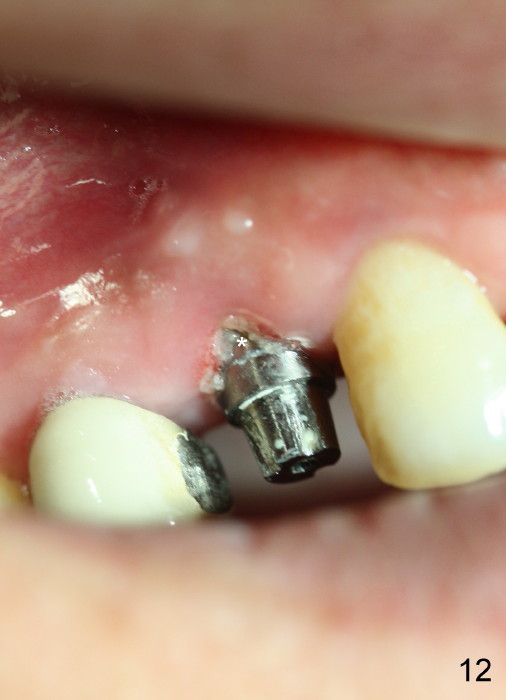

Eighteen days postop, the patient returns for #4 root canal therapy; PA shows bone graft next to the implant (Fig.11 *). Twenty-two days postop, the immediate provisional is dislodged with loss of bone graft over the middle of the buccal surface of the implant (Fig.12 *). The implant and abutment are prepared so that the margin is advanced apically (Fig.13 ^) with accentuation of the retention grooves (*). The provisional is relined and recemented.